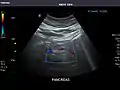

Abdominal ultrasound can be used to diagnose abnormalities in various internal organs, such as the kidneys,[1] liver, gallbladder, pancreas, spleen and abdominal aorta. If Doppler ultrasonography is added, the blood flow inside blood vessels can be evaluated as well (for example, to look for renal artery stenosis). It is commonly used to examine the uterus and fetus during pregnancy; this is called obstetric ultrasonography.[2][3]

Aorta: Visualized portions normal in caliber, 16 x 15 mm.